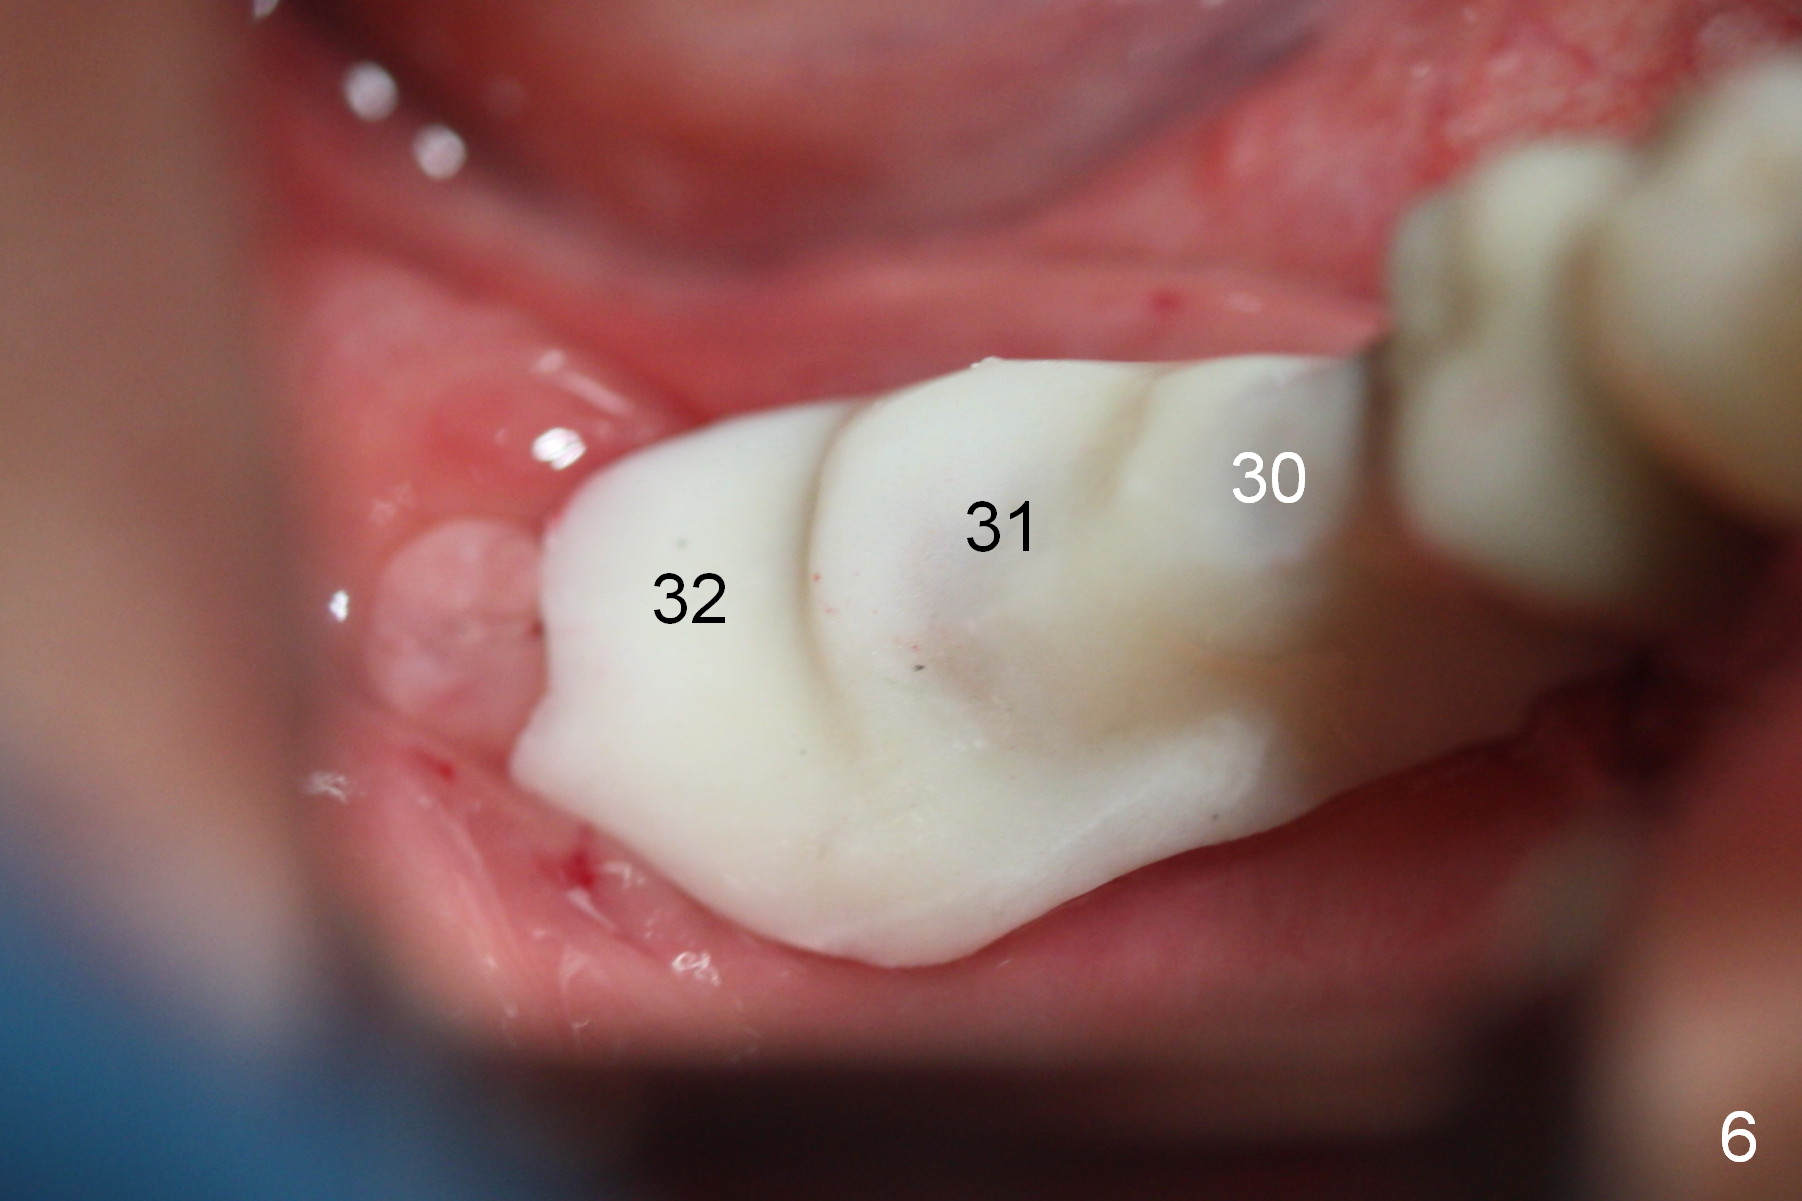

A preop photo shows different shape of pontics at #30 and 31 (Fig.1 <), suggesting different width of the edentulous ridge.  Two of 8 mm parallel pins are inserted for position and trajectory (Fig.2 (red dashed line: the superior border of the Inferior Alveolar Canal).  When they are removed from the osteotomy sites, the narrow ridge at #30 is shown (Fig.3).  A 3x12 mm 1-piece implant is placed at #30, while a 4.5x10 mm 2-piece one at #31 (Fig.4,5).  It appears that it is necessary to place an implant at #32, since the tooth #1 is present (Fig.5).  The suggestion is rejected by the patient due to finance.  After extraction of the tooth #32 and insertion of collagen plug, an immediate splinted provisional is fabricated to cover the #32 socket as well (Fig.6).  The provisional is modified (to remove the portion that covers #32 socket) 3-4 weeks postop.